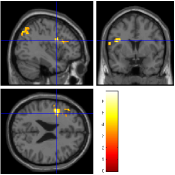

For the aC-aS contrast, Fig. 9 [top] shows, for the most significant slice and , that all pMRI reconstruction algorithms succeed in finding evoked activity in the left parietal and frontal cortices, more precisely in the inferior parietal lobule and middle frontal gyrus according to the AAL template666available in the xjView toolbox of SPM5.. Tab. 3 also confirms a bilateral activity pattern in parietal regions for . Moreover, for , Fig. 9 [bottom] illustrates that our pipeline (UWR-SENSE and 4D-UWR-SENSE) and especially the proposed 4D-UWR-SENSE scheme enables to retrieve reliable frontal activity elicited by mental calculation, which is lost by the the mSENSE algorithm. From a quantitative viewpoint, the proposed 4D-UWR-SENSE algorithm finds larger clusters whose local maxima are more significant than the ones obtained using mSENSE and UWR-SENSE, as reported in Tab. 3. Concerning the most significant cluster for , the peak positions remain stable whatever the reconstruction algorithm. However, examining their significance level, one can first measure the benefits of wavelet-based regularization when comparing UWR-SENSE with mSENSE results and then additional positive effects of temporal regularization and 3D wavelet decomposition when looking at the 4D-UWR-SENSE results. These benefits are also demonstrated for .

| mSENSE | UWR-SENSE | 4D-UWR-SENSE | |

|---|---|---|---|

|

|

|

|

|

|

|

| cluster-level | voxel-level | |||||

| p-value | Size | p-value | T-score | Position | ||

| mSENSE | 320 | 6.40 | -32 -76 45 | |||

| 163 | 5.96 | -4 -70 54 | ||||

| 121 | 6.34 | 34 -74 39 | ||||

| 94 | 6.83 | -38 4 24 | ||||

| UWR-SENSE | 407 | 6.59 | -32 -76 45 | |||

| 164 | 5.69 | -6 -70 54 | ||||

| 159 | 5.84 | 32 -70 39 | ||||

| 155 | 6.87 | -44 4 24 | ||||

| 4D-UWR-SENSE | 454 | 6.54 | -32 -76 45 | |||

| 199 | 5.43 | -6 26 21 | ||||

| 183 | 5.89 | 32 -70 39 | ||||

| 170 | 6.90 | -44 4 24 | ||||

| mSENSE | 58 | 0.028 | 5.16 | -30 -72 48 | ||

| UWR-SENSE | 94 | 0.003 | 5.91 | -32 -70 48 | ||

| 60 | 0.044 | 4.42 | -6 -72 54 | |||

| 4D-UWR-SENSE | 152 | 6.36 | -32 -70 48 | |||

| 36 | 0.009 | 5.01 | -4 -78 48 | |||

| 29 | 0.004 | 5.30 | -34 6 27 | |||

Fig. 10 illustrates another property of the proposed pMRI pipeline, i.e. its robustness to the between-subject variability. Indeed, when comparing subject-level Student’s -maps reconstructed using the different pipelines (), it can be observed that the mSENSE algorithm fails to detect any activation cluster in the expected regions for the second subject (see Fig. 10 [bottom]). By contrast, our 4D-UWR-SENSE method retrieves more coherent activity while not exactly at the same position as for the first subject.